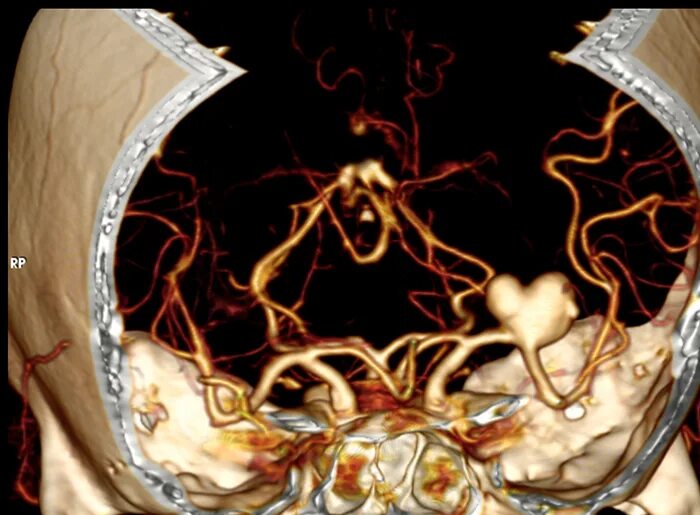

Томография сосудов головного мозга